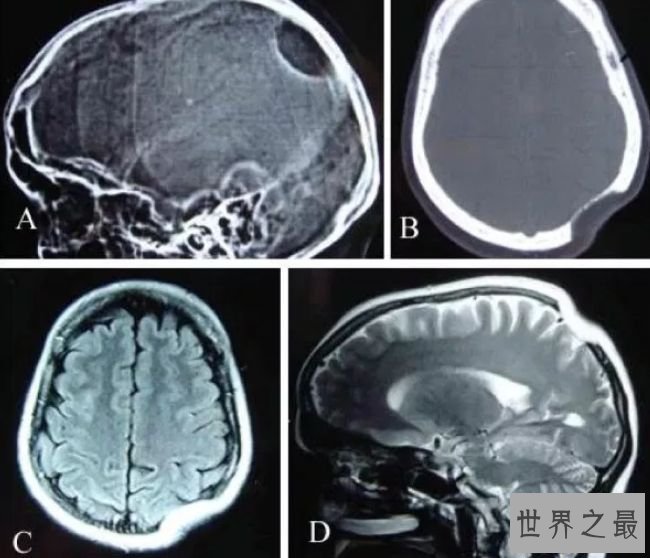

5.蜡泪样骨病

人类骨骼中最不常见的疾病之一是蜡泪样骨病,这种疾病在人类中十分稀有。在这种疾病中,一种十分巩固的骨头会在已经存在的骨头上以不规则的模式生长,在x射线钻研中,这种骨骼的生长看起来像蜡烛外表的蜡泪。